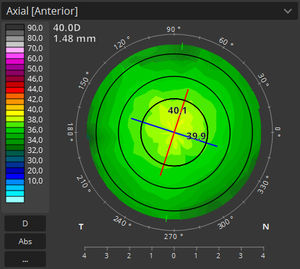

... asociados al modelado de la superficie posterior de la córnea. El módulo SOCT T-OCT proporciona mapas axiales, tangenciales, de potencia total, de altura, de epitelio y de espesor corneal. El módulo de ...

Optopol Technology